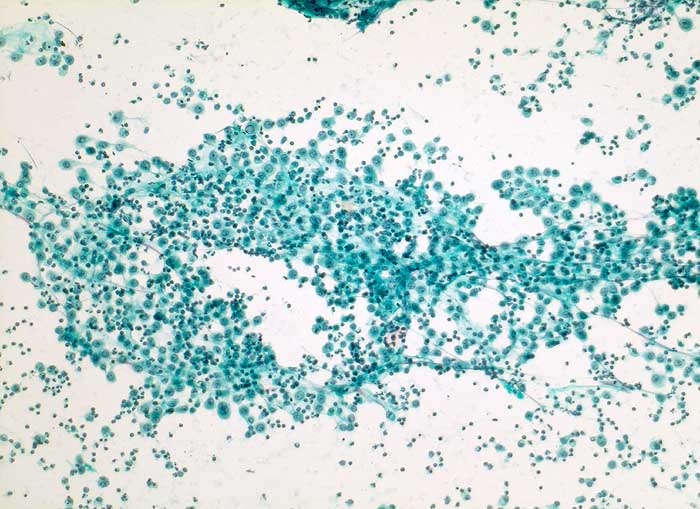

Reaktiv veränderte Mesothelzellen

Irritierte Mesothelzellen beginnen zu proliferieren. Die Zellen werden plump und kubisch, die Kerne sind vergrössert. Diese reaktiven Mesothelien können mit Karzinomzellen verwechselt werden. Mesothelzellen können Tumoren imitieren, indem sie kleine Gruppen, Pseudoverbände, Zellballen, Pseudopapillen, "cell in cell" und "Indian files" ausbilden. Unter reaktiven Bedingungen kommen sehr grosse und mehrkernige Mesothelzellen vor. In Zweifelsfällen empfiehlt sich eine immunzytochemische Untersuchung mit Calretinin (Mesothelien positiv) und BerEP4 (Karzinomzellen positiv).